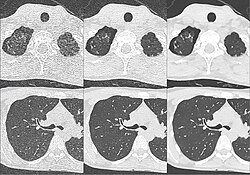

Kombination aus multiplanarer Reformatierung und sliding thin slab. Der Bildkursor befindet sich in der Harnblase. Die Originalschichtdicke beträgt 1,25 mm, dargestellt wird in allen Ansichten gemittelt (= average) in 3,7 mm bzw. 3,8 mm Dicke. -

Kombination aus multiplanarer Reformatierung und sliding thin slab. Der Bildkursor befindet sich im rechten Lungenflügel. Die sts-Bildstapel werden in Form von MIP-Darstellungen gezeigt (STS-MIP).[52] Links oben befindet sich eine VR-Darstellung der Lunge; sie zeigt einen Blick auf die koronal an Kursorposition geschnittene Lunge. -